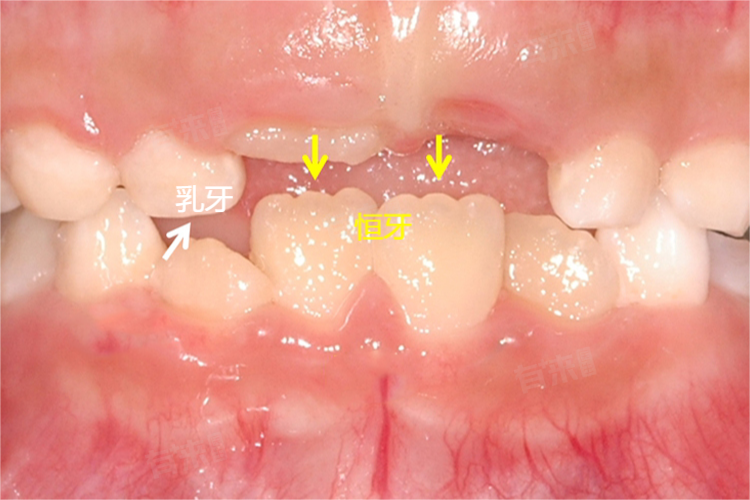

4、替换周期:乳牙的替换周期始于儿童大约6岁左右,此时第一颗恒牙开始萌出,直至12岁左右完成全部替换,这一过程被称为混合牙列期。恒牙一旦萌出,除非因为意外损伤或其他疾病原因被拔除,否则将伴随个体终生。